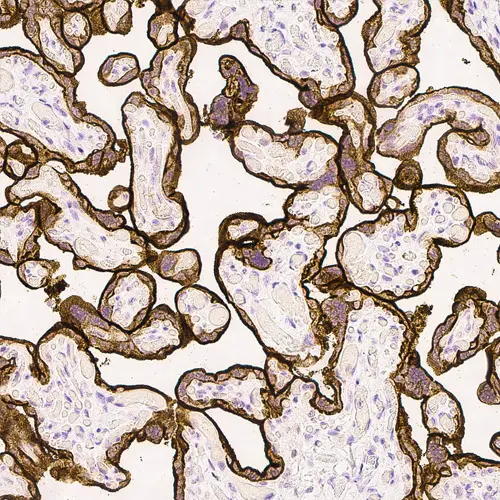

Human placenta: immunohistochemical staining for Epidermal Growth Factor Receptor. High expression of EGFR localized in the trophoblastic layer of the placental villi. Epidermal Growth Factor Receptor: clone EGFR.113

Product Specific Information Clone EGFR.113 is raised to the extracellular domain of the EGFR molecule.